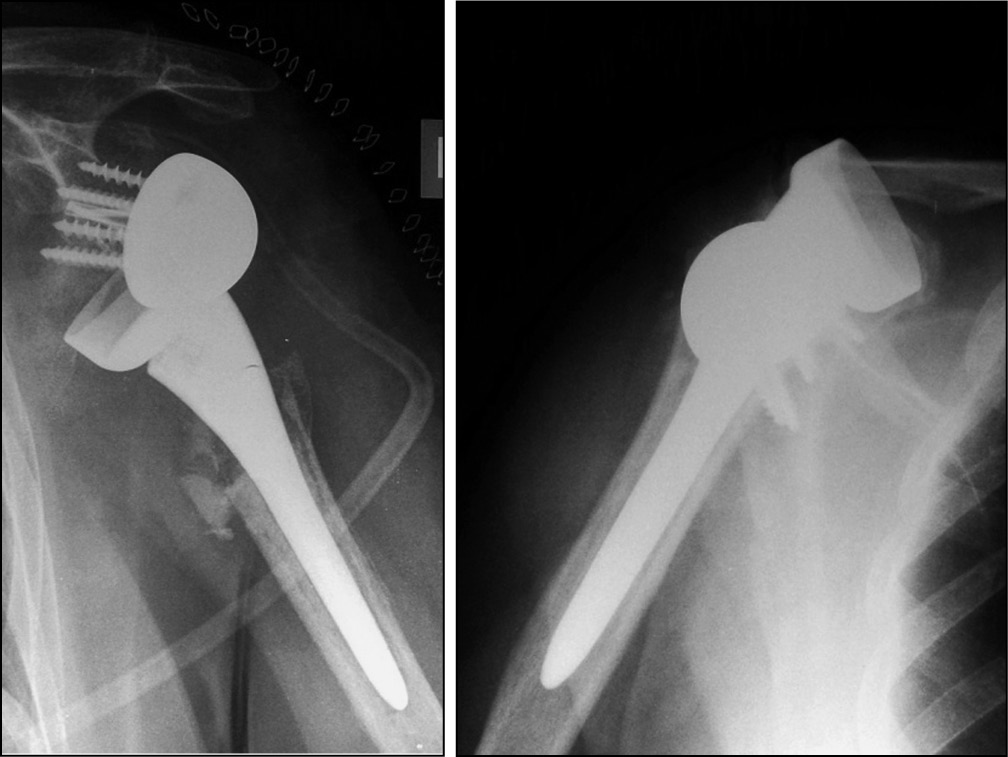

При клиническом и рентгенологическом обследовании пациентов выявлено 2 случая (8,7 %) перипротезного перелома, 1 из которых произошел интраоперационно. У 3 пациентов (13,2 %) выявлен вывих эндопротеза: зафиксировано 2 случая вывиха плечевого компонента, вследствие ранних сроков нагрузок и объемов движений прооперированной конечности (рис. 1), а 1 пациент пострадал от разобщения гленосферы с метагленом, и в последствие ее вывихом (рис. 2).

Рис. 1. Рентгенограммы пациентов с вывихом плечевого компонента реверсивного эндопротеза плечевого сустава

Fig. 1. Patients’ X-ray with shoulder component dislocation of a reverse shoulder joint endoprosthesis